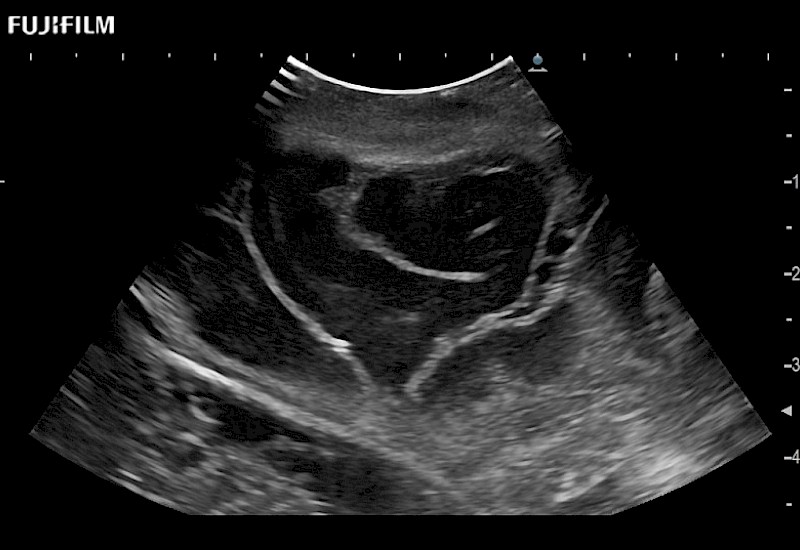

Smaller footprint (20mm) curved array transducer that is ideal for scanning during cranial guidance procedures.

Exclusive 10mm side‐fire linear array transducer with 2.87mm diameter is ideal for real‐time visualization through and behind structures and instant, scalable definition of anatomy and vascularity including the ability to delineate and define tumor margins.